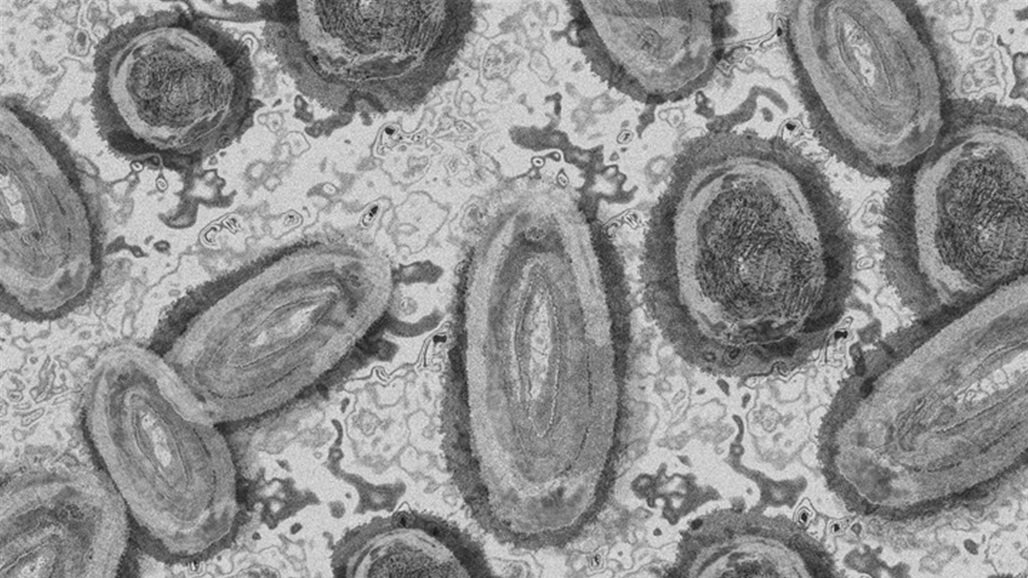

تسجيل أول إصابة مؤكدة بـ "جدري القرود" في أيرلندا

بغداد - كلمة الإخباري: أعلنت وكالة الصحة في أيرلندا، السبت، تسجيل أول إصابة مؤكدة بجدري القردة في البلاد.

وأعلنت حوالي 20 دولة لا يتوطن فيها جدري القرود عن رصد بؤر للمرض الفيروسي، مع تسجيل أكثر من 200 حالة إصابة مؤكدة أو مشتبه بها معظمها في أوروبا.